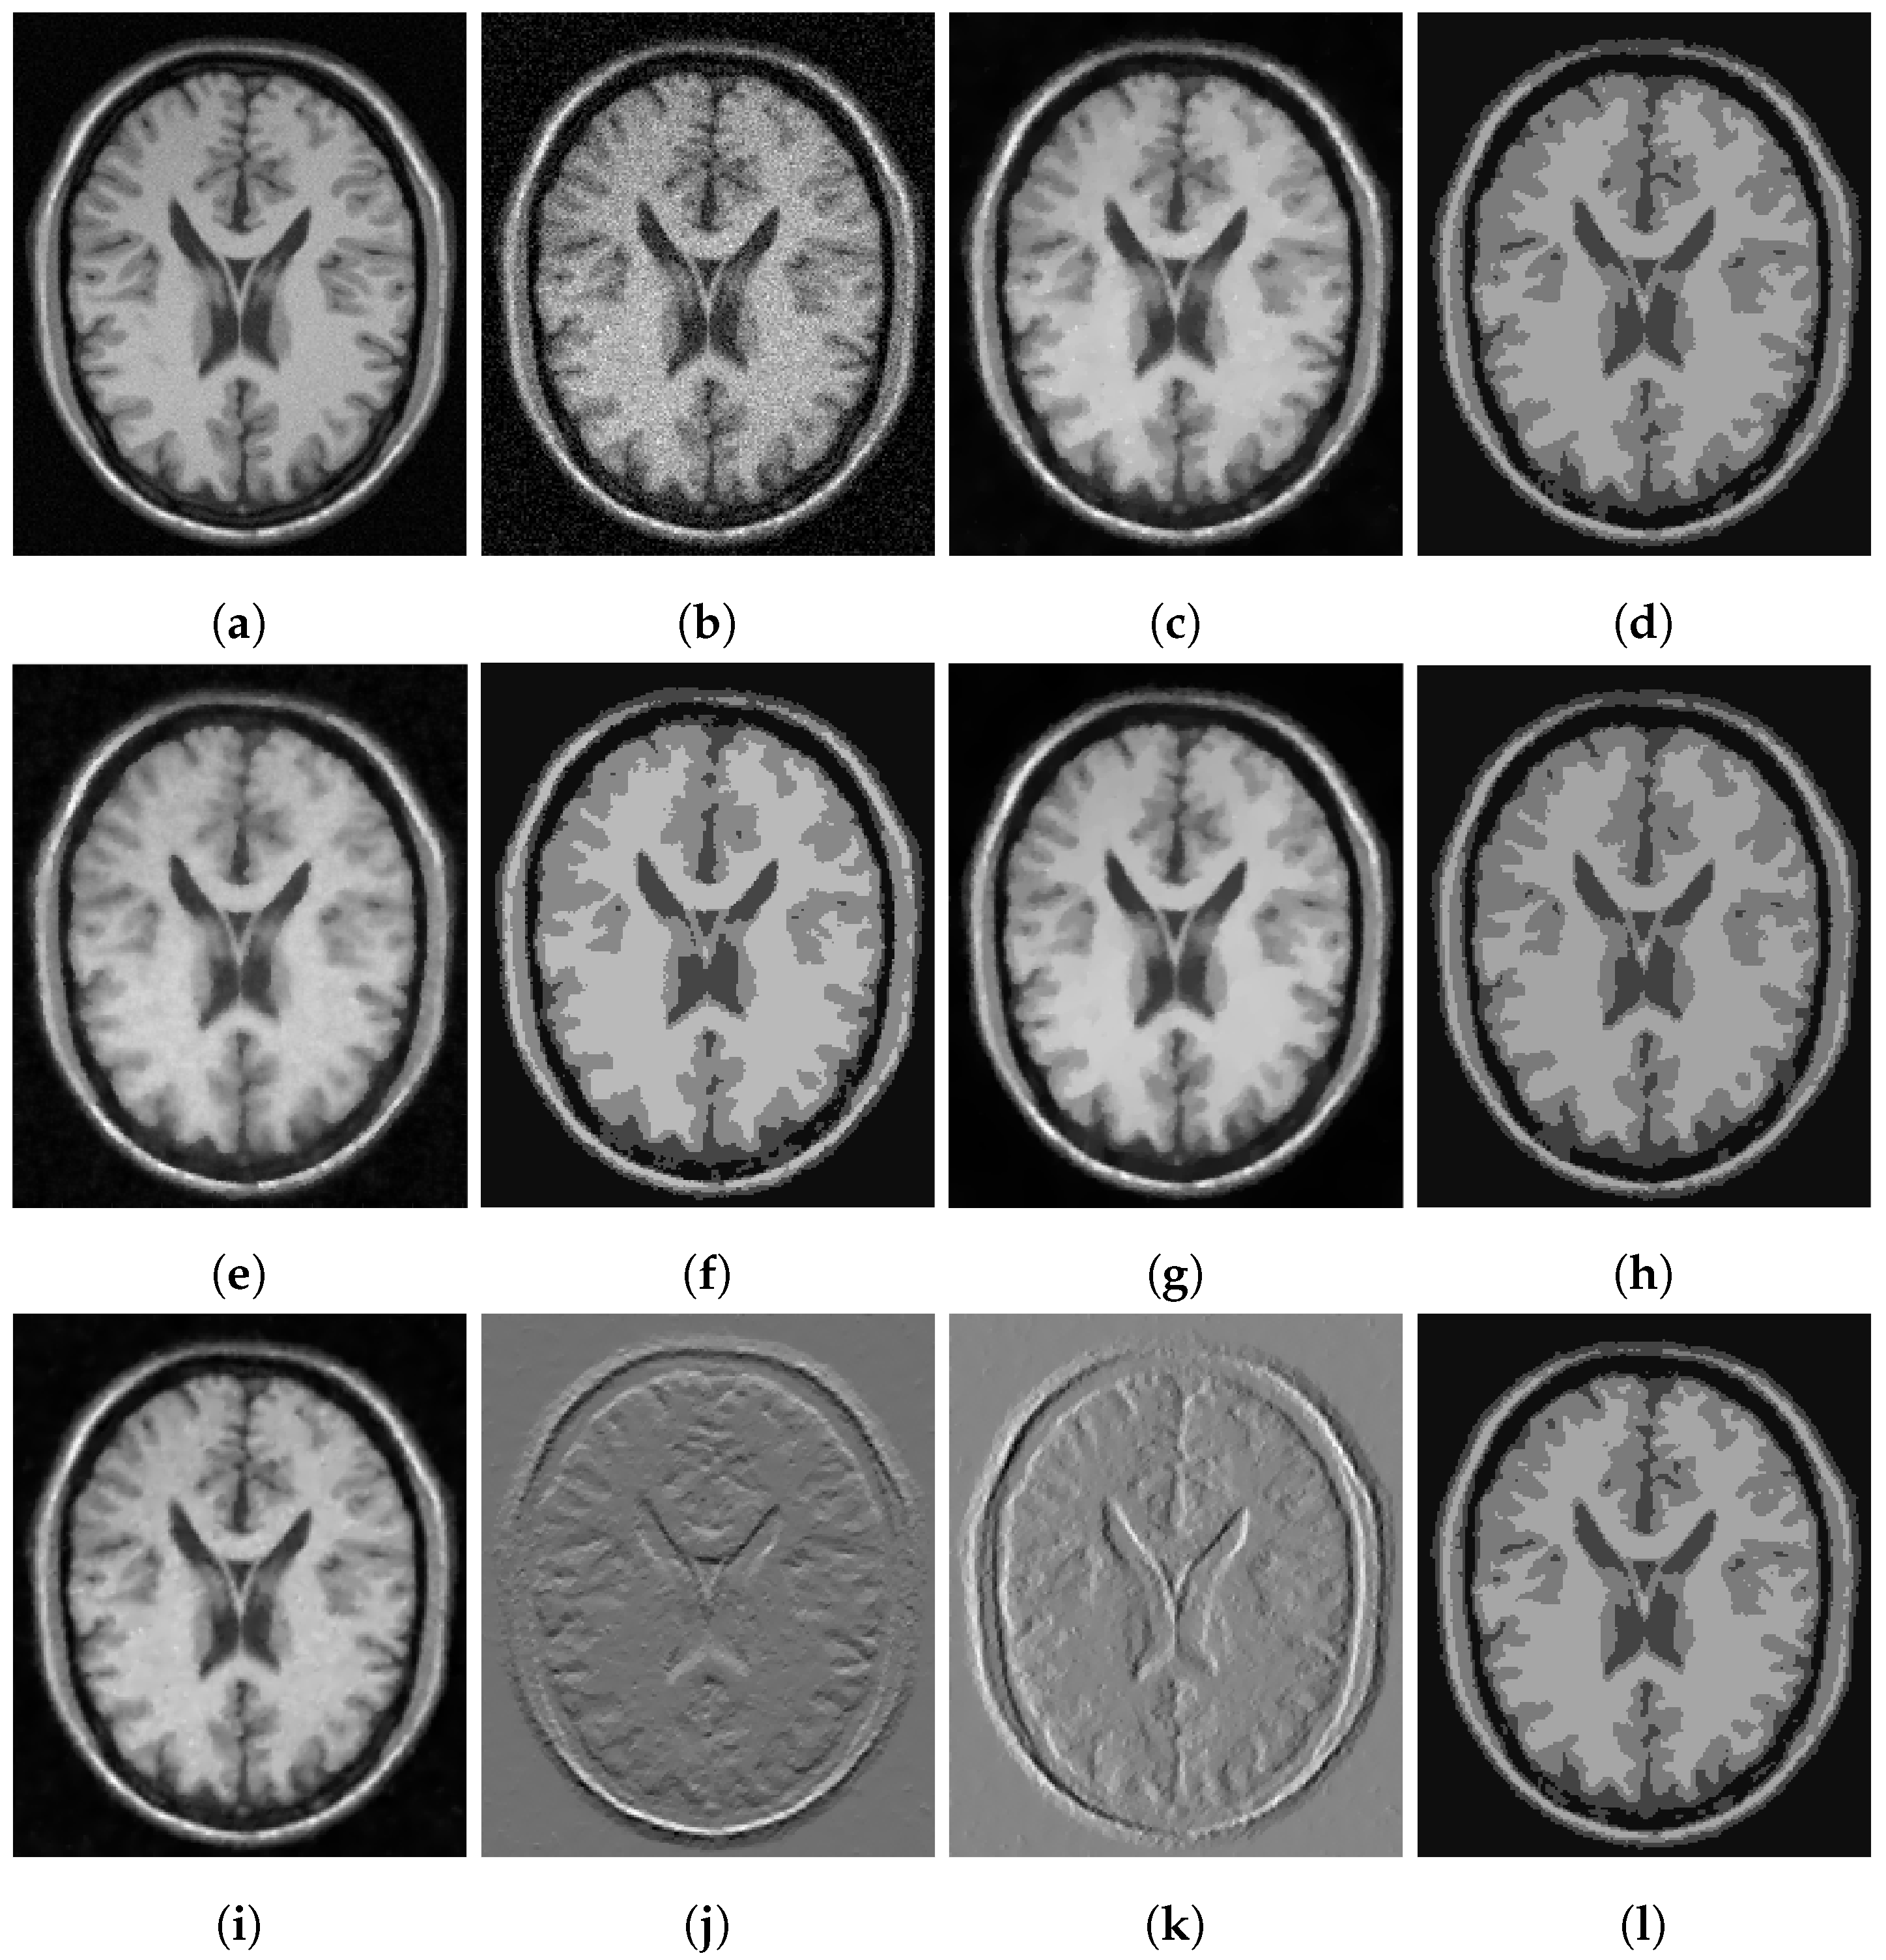

In Figure 3, Figure 4 and Figure 5, we show some examples of multiphase segmentation on MRI images of the brain. In all cases, we add Gaussian noise with mean 0 and standard deviation 17 and run the noisy image as input to both for all models but the CRCV model (as this is a two-phase model only). The output is then given as input to the k-means algorithm with . We show the clustering output in the final column of the relevant figures. We see that the segmentation result of our model is better at finding some of the finer edges; for example, the white matter segmentation from our model is in general more detailed than the segmentation from the competing ones.

Figure 3.

MRI segmentation: (a) Clean image. (b) Noisy image used as input to the models. (c) Output of CCZ. (d) CCZ after thresholding. (e) Output of CNC. (f) CNC after thresholding. (g) Output of T-ROF. (h) T-ROF after thresholding. (i) Output g of our model. (j) Output of our model. (k) Output of our model. (l) Ours after thresholding.